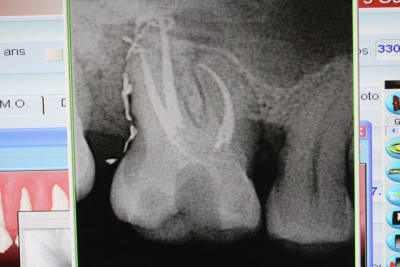

un cas réalisé depuis : une endocouronne réalisée la semaine dernière sur une nécrose d'origine paro ,

surfaçage + laser pendant la cuisson , a voir dans le temps...

C'est un joli cas mais ce n'est pas une endocouronne , c'est une couronne-endo très différent du point de vue comportement mécanique. Il aurait été possible d'être moins agressif en faisant une endo-V-Prep.

La couronne endo est une composition qui existe quand on a du mal a abandonner l'ancien monde, mais qu'on est conscient qu'il y a de nouvelles solutions !!